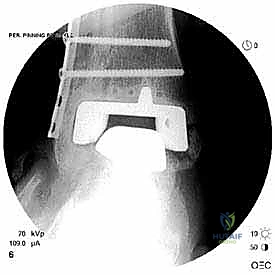

- الأشعة السينية مع تحميل الوزن (Weight-bearing X-rays): لتقييم الزوايا الميكانيكية وتحديد مدى هبوط المفصل أو وجود كسور في الكعب.

علاج هذه الكسور يتطلب مهارة فائقة من الدكتور محمد هطيف، حيث يتم استخدام تقنيات الجراحة الميكروسكوبية وتثبيت الكسور باستخدام صفائح معدنية دقيقة ومسامير (Locking Plates) دون المساس بثبات المفصل الصناعي، أو يتم دمج علاج الكسر ضمن عملية مراجعة المفصل الكلية إذا كان المفصل نفسه تالفاً.

يتم تخدير المريض (نصفياً أو كلياً) واستخدام عاصبة (Tourniquet) لتقليل النزيف. يتم تعقيم الطرف السفلي وتجهيز أجهزة الأشعة المرئية (C-arm) داخل الغرفة.

يتم إدخال المفصل الجديد المخصص للمراجعة، والذي يحتوي غالباً على سيقان (Stems) تدخل عميقاً في عظمة الساق وعظمة الكاحل لضمان الثبات الميكانيكي. في حال وجود كسور في الكعب، يتم تثبيتها في هذه المرحلة.

الخطوة السادسة: الإغلاق التجميلي

يتم خياطة الأربطة والأنسجة الرخوة والجلد بطرق تجميلية دقيقة لتقليل الندبات وسرعة الالتئام، ثم توضع القدم في جبيرة خلفية واقية.